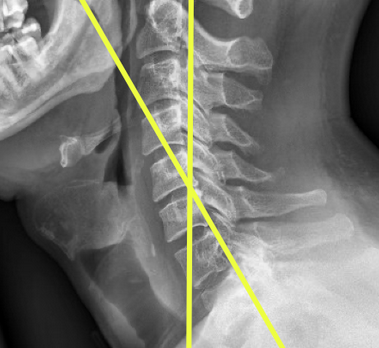

Image Type Cervical Spine X-Ray CT Scan MRI Scan Atlantodental Interval (ADI) Basion-Axial Interval Basion-Dens Interval (BDI) C2 Tilt C2–C7 Coronal Cobb Angle Cervical C2-7 lordosis C2-C7 Translation Chamberlain’s Line / McGregor’s Line Flexion-Extension George’s Line (Posterior Cervical Line) K-Line Interpedicular Distance (IPD) Occiput-C2 Angle Occipital Condyle–C1 Interval (CCI) Posterior Atlantodental Interval (PADI) Power’s ratio Sagittal Canal Diameter Sagittal Vertical Axis (SVA) Spinolaminar line Swischuk Line T1 Slope Torg/Pavlov Canal-to-Body Ratio